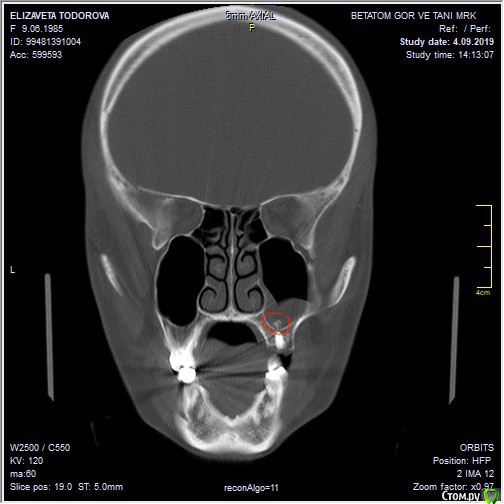

elizaveta73 Опубликовано 5 сентября, 2019 Автор Поделиться Опубликовано 5 сентября, 2019 Какое инородное тело вы имеете ввиду? вот это в пазухе. Ссылка на комментарий

krokomot Опубликовано 5 сентября, 2019 Поделиться Опубликовано 5 сентября, 2019 Это судя по всему костнопластический материалл или может быть пломбировочный, ни то ни другое не нуждается в радикальной операции на синусе. Ссылка на комментарий